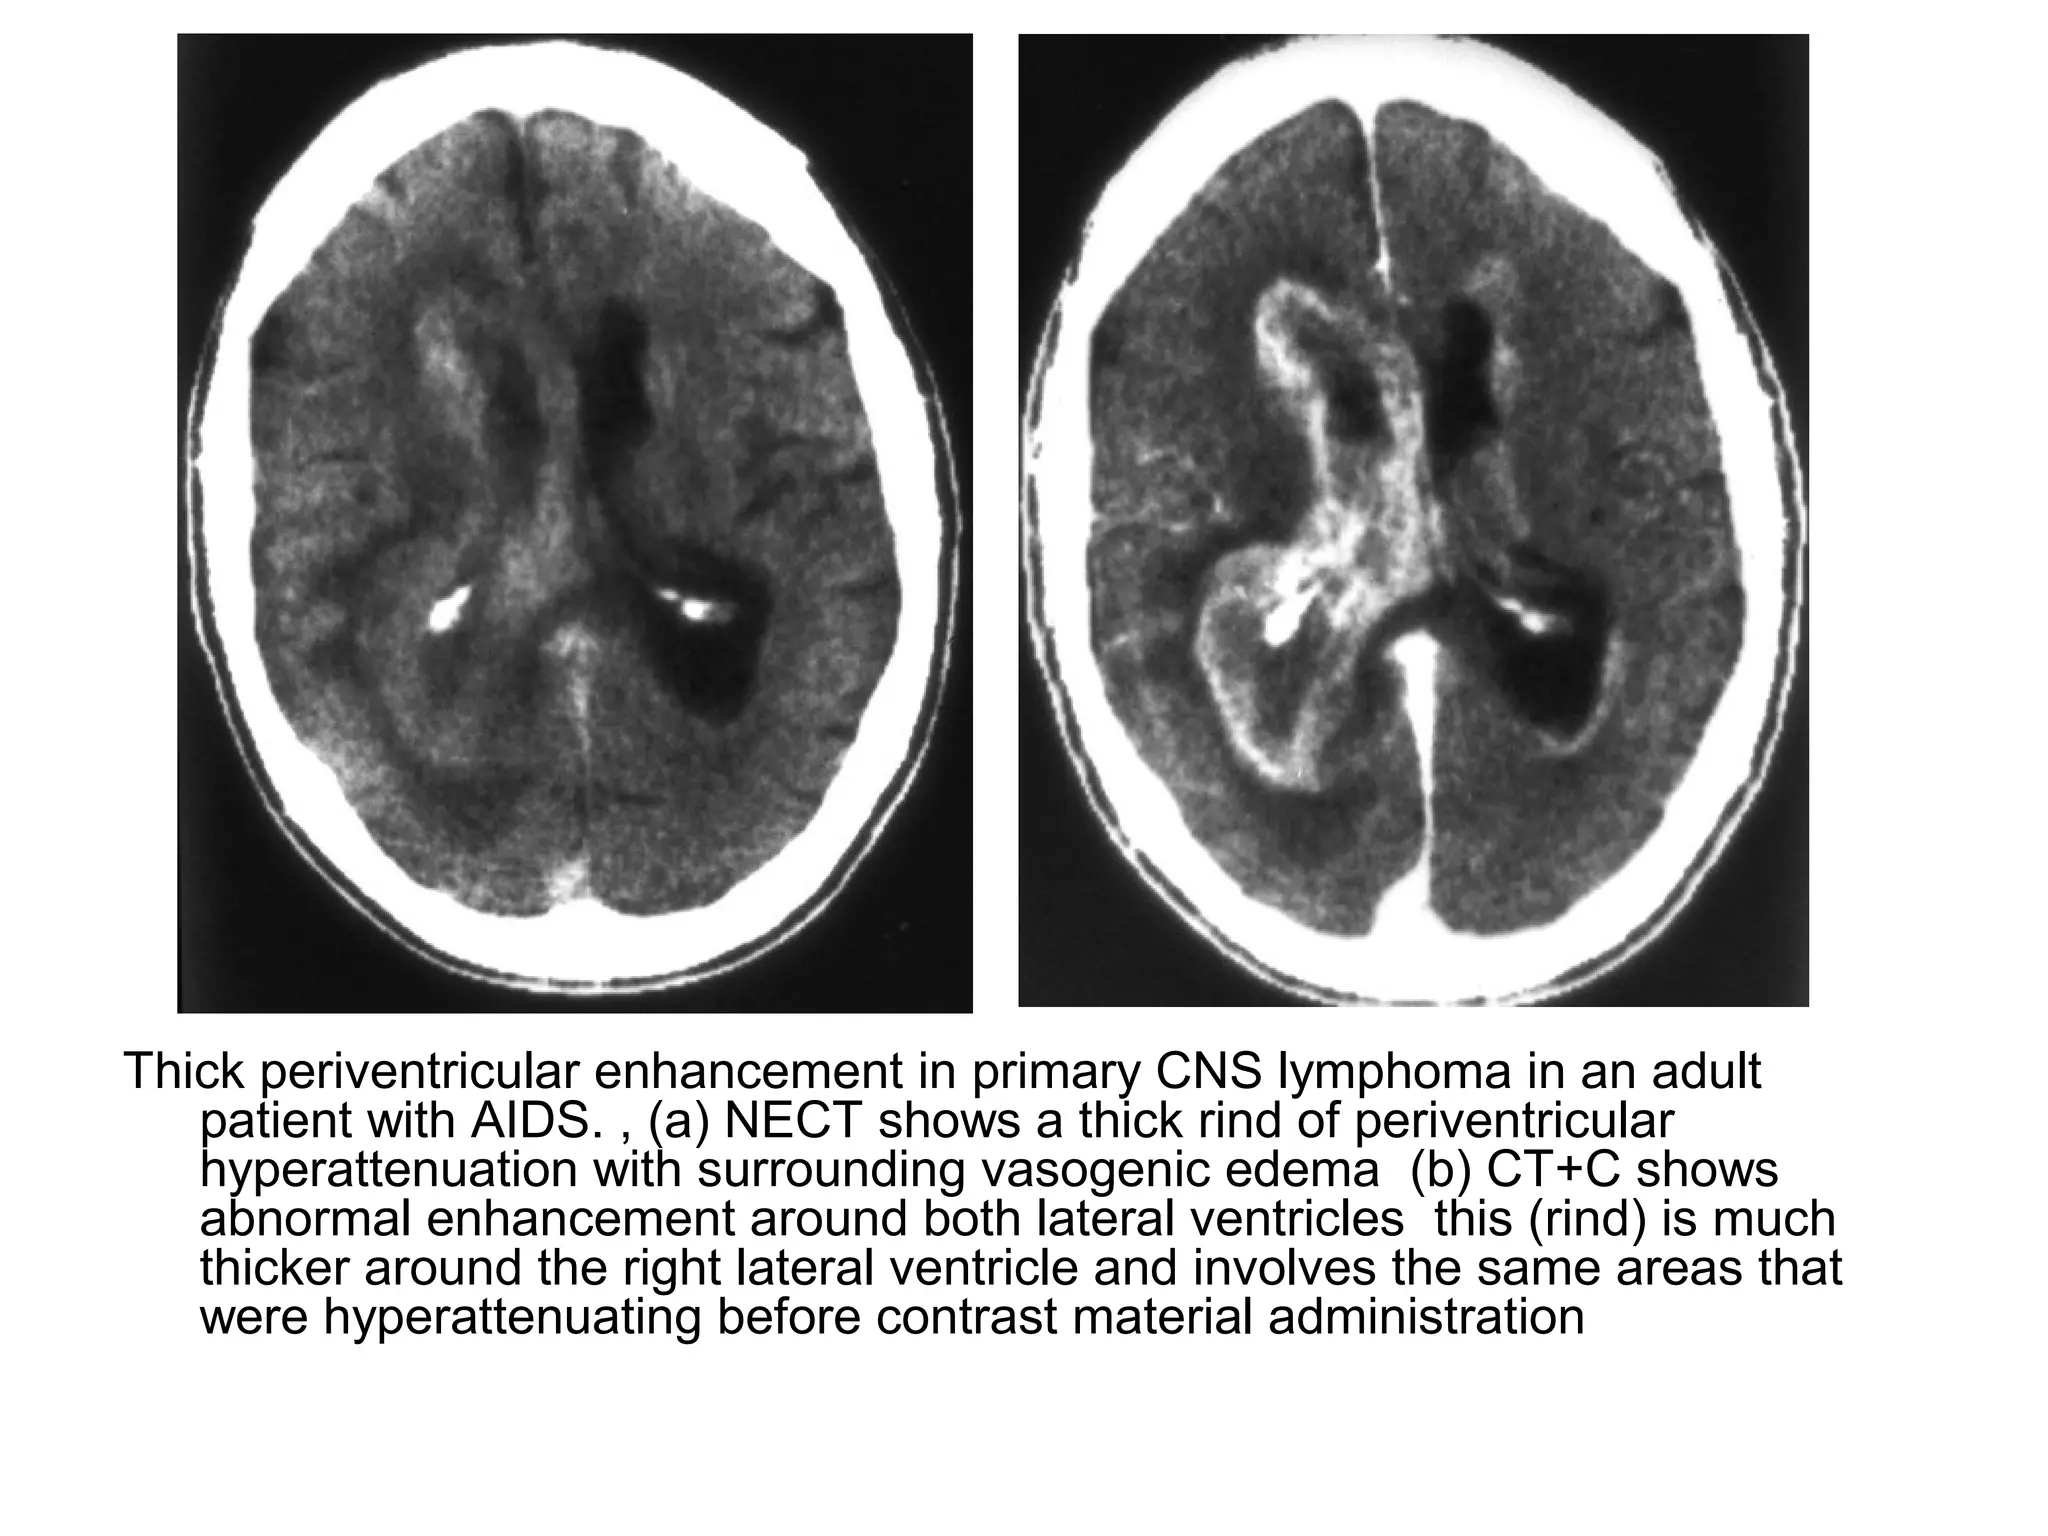

Thick periventricular enhancement in primary CNS lymphoma in an adult

patient with AIDS. , (a) NECT shows a thick rind of periventricular

hyperattenuation with surrounding vasogenic edema (b) CT+C shows

abnormal enhancement around both lateral ventricles this (rind) is much

thicker around the right lateral ventricle and involves the same areas that

were hyperattenuating before contrast material administration